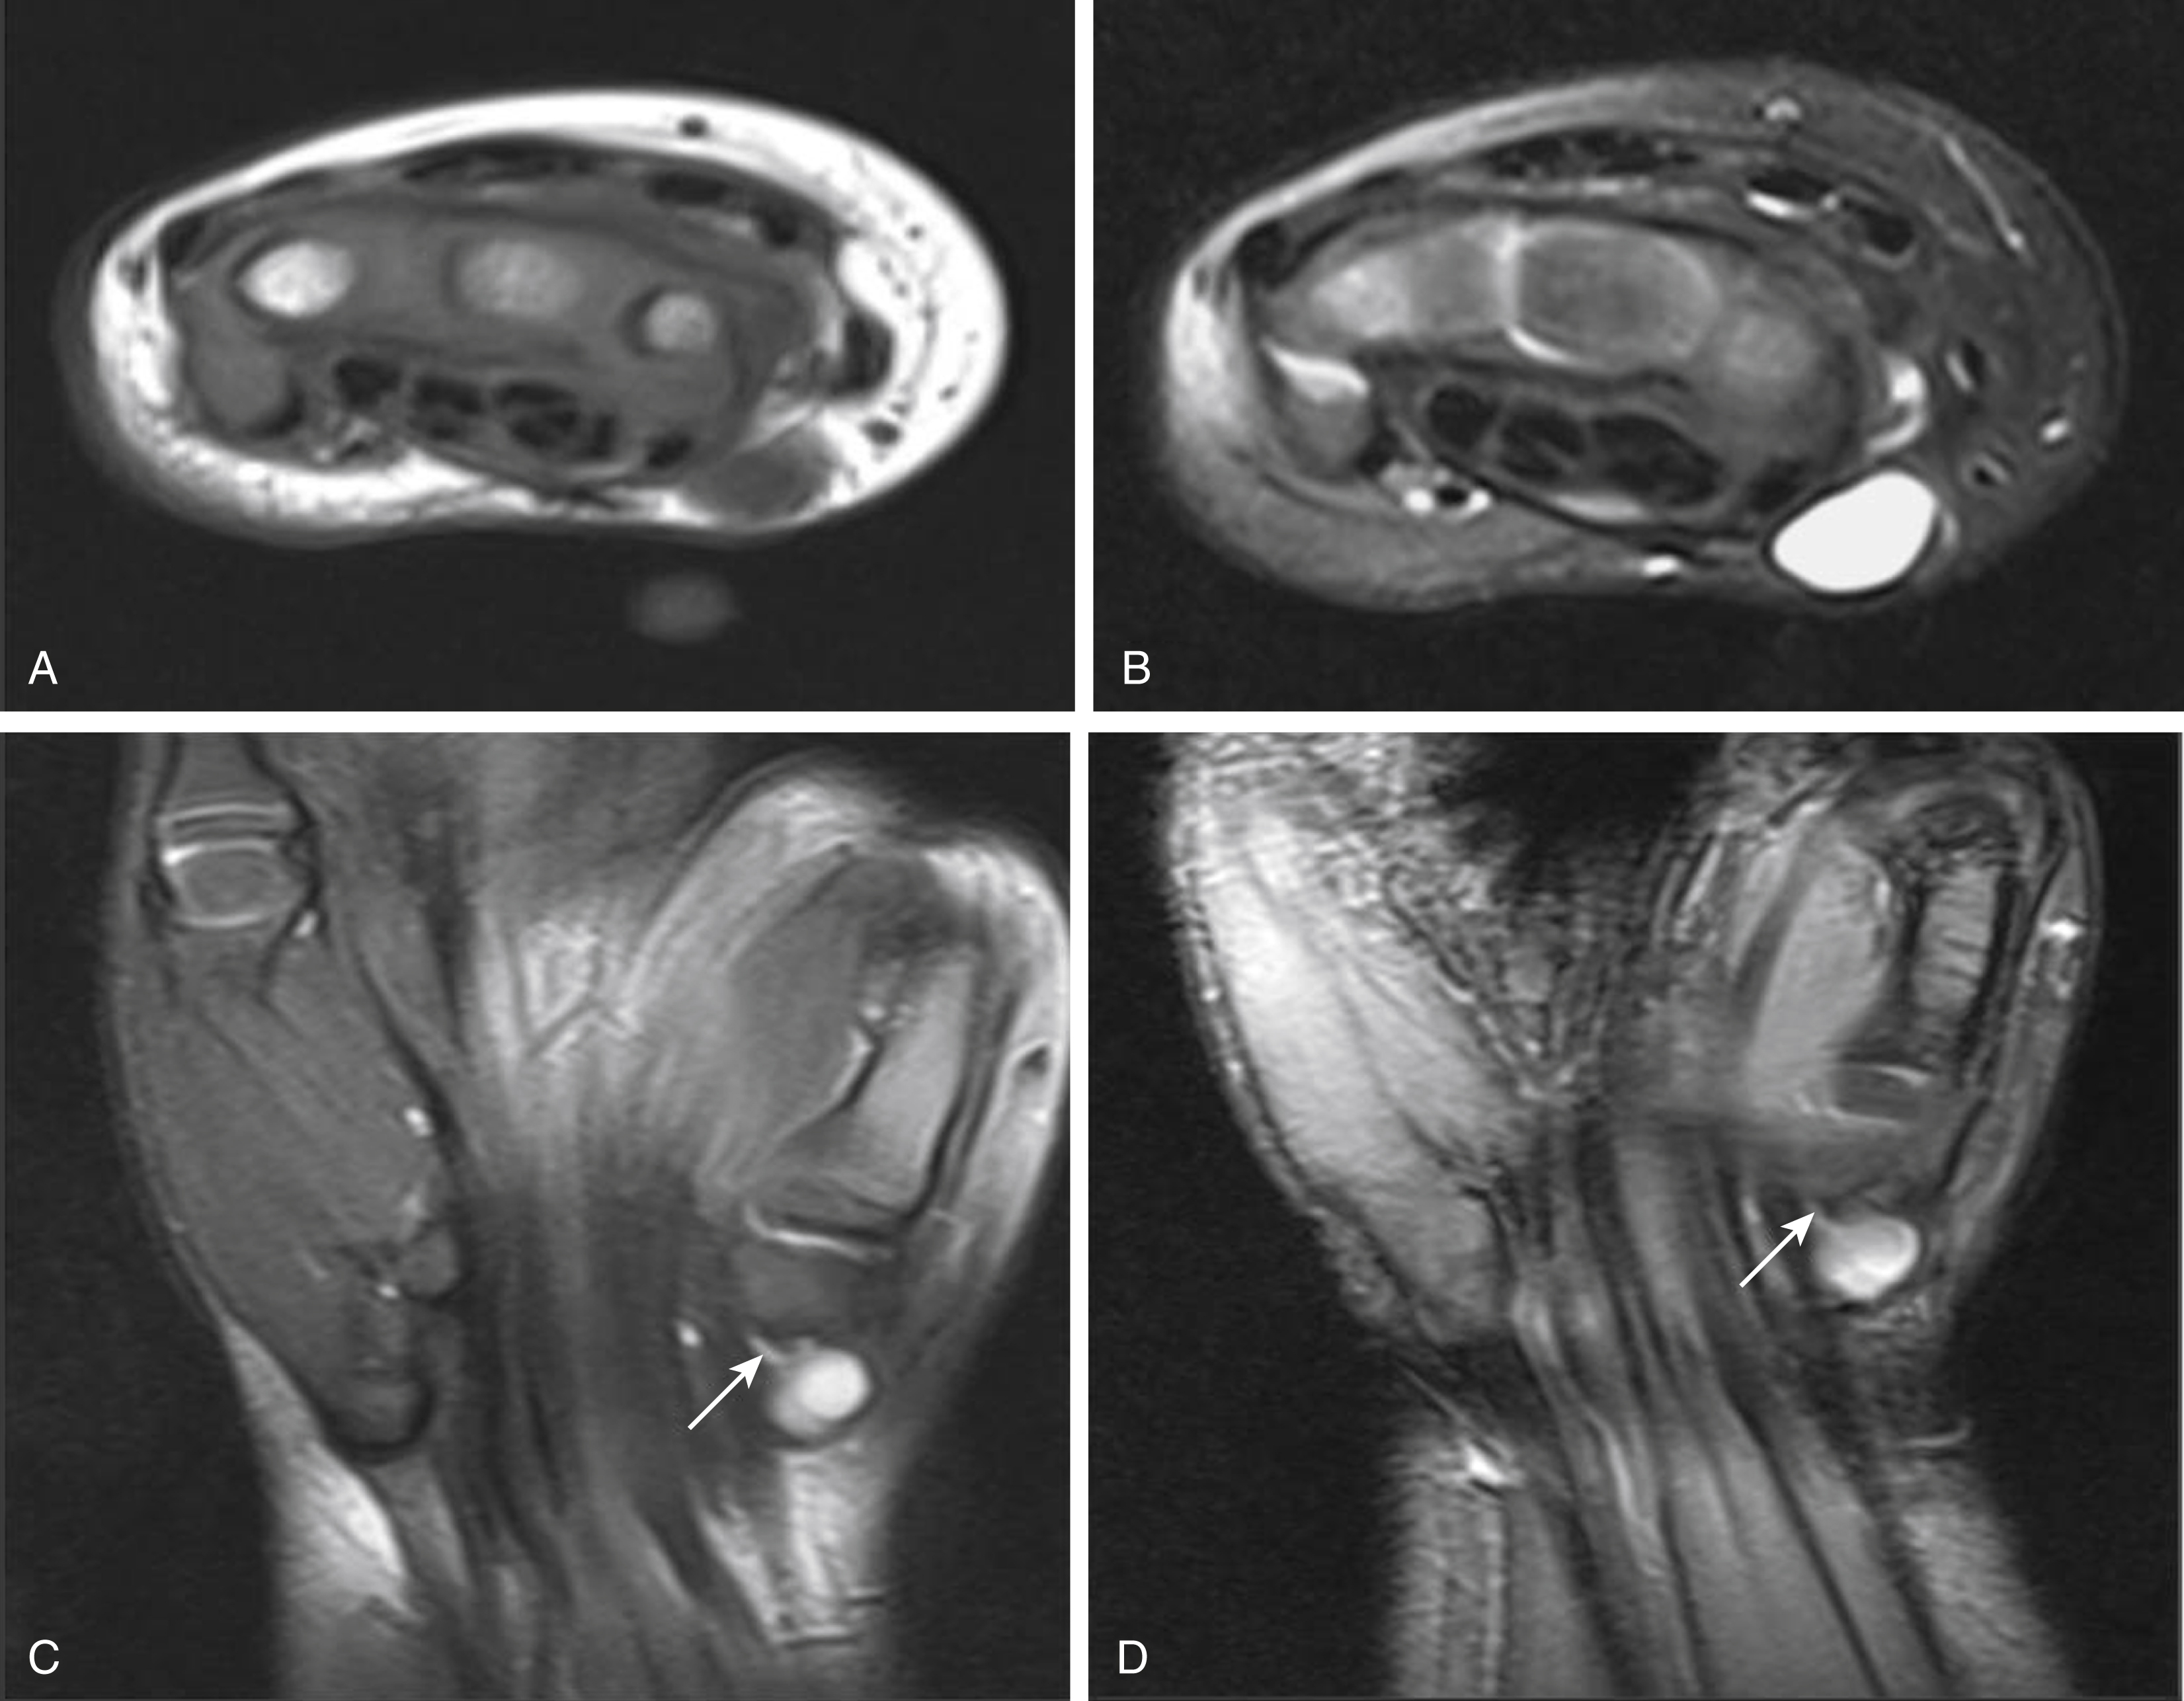

Ganglion cysts are lesions with a dense fibrous connective tissue capsule lined with flat spindle-shaped cells. Although imaging of these lesions usually shows a simple cyst, septations may be present. Characteristics on imaging that may suggest a ganglion cyst include internal septa with peripheral fluid-filled pseudopodia that shows up as a “bunches of grapes” appearance. Typically, T1-weighted imaging of a ganglion shows intermediate to high signal intensity because of the content being either mucinous or hemorrhagic. T2-weighted sequences will show homogeneous high signal ( Fig. 16.1 ). US will show a similar cystic appearance, and color Doppler imaging may show vascularity of the septa on low-flow settings. Although controversial, ganglion cysts are thought to arise from mucoid cystic degeneration in a collagenous structure under repetitive stress, and hence most commonly occur in the hand, wrist, and foot. The joint capsule and tendon incur the majority of the stress from repetitive activities and results in the periarticular soft tissue being prone to developing ganglia. Ganglion cysts may also occur in intraarticular, intraosseous, or periosteal locations.

Fig. 16.1, Five-year-old with palpable lump of the wrist with magnetic resonance imaging T1- (A) and T2-weighted (B) axial images and coronal T2-weighted (C) and proton density (D) sequences showing a cystic structure adjacent to the volar midcarpal row with a thin tail ( arrow ) consistent with a ganglion cyst.

Ganglion cysts are less common in children than in adults. When present, these lesions are usually asymptomatic. Management is conservative due to the tendency for ganglion cysts to spontaneously resolve, especially in the pediatric population. Repeated trauma, however, can result in progression of these masses and can lead to them becoming symptomatic or eroding adjacent bone.